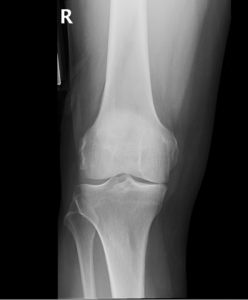

Your doctor will diagnose osteoarthritis based on the medical history, physical examination, and X-rays. X-rays typically show a narrowing of joint space in the arthritic knee.

Osteoarthritis is the most common form of knee arthritis in which the joint cartilage gradually wears away. It most often affects older people. In a normal joint, articular cartilage allows for smooth movement within the joint, whereas in an arthritic knee the cartilage itself becomes thinner or completely absent. In addition, the bones become thicker around the edges of the joint and may form bony “spurs”. All of these factors can cause pain and restricted range of motion in the joint.